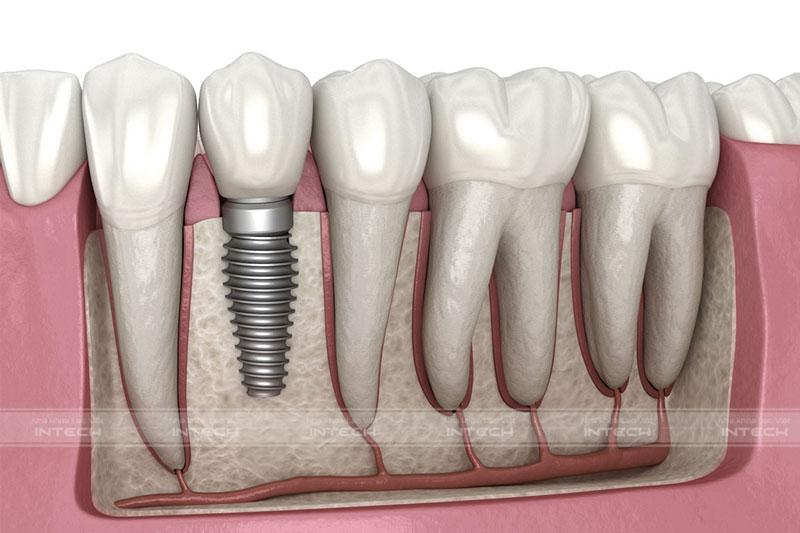

Trồng răng Implant là phương pháp khôi phục răng mất cố định, được thực hiện bằng cách phẫu thuật đặt trụ Implant được làm từ vật liệu Titanium vào trong xương hàm. Sau khi chờ một thời gian để trụ Implant tích hợp với xương hàm, bác sĩ sẽ tiến hành lắp khớp nối Abutment và phục hình răng sứ bên trên.

Kỹ thuật trồng răng ImplantKỹ thuật trồng răng Implant